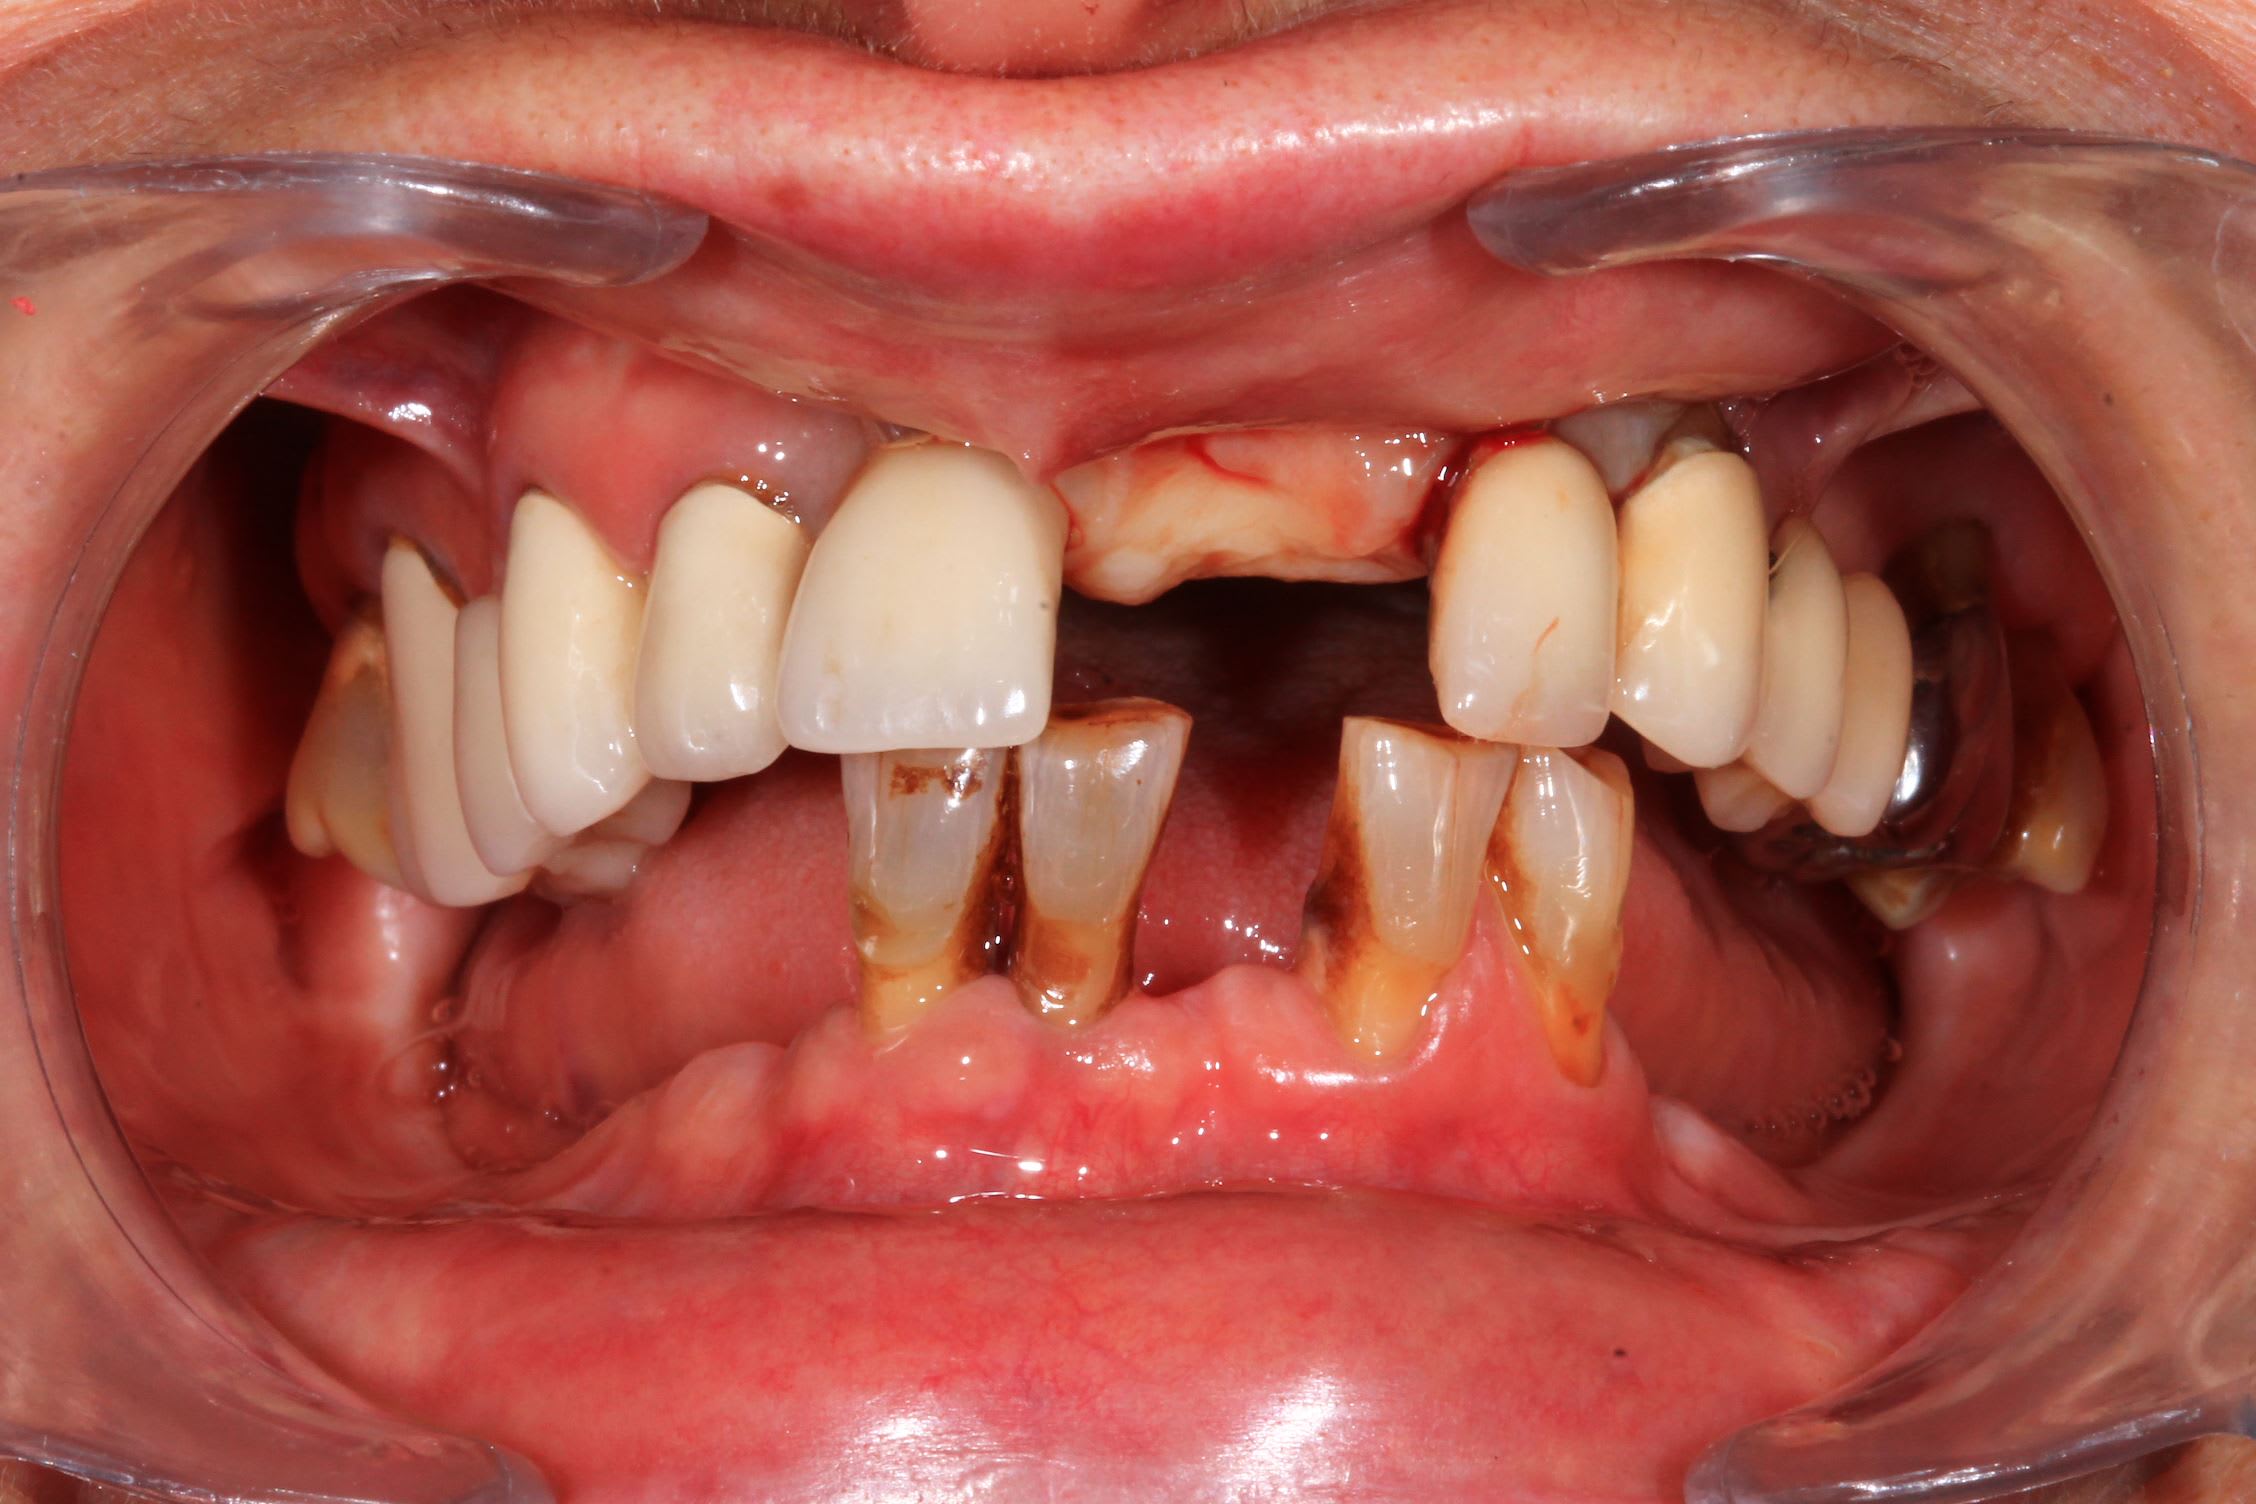

Un cas de mise en charge instantané, façon Dimitri Pascual.

Mais quand on a pas Co-diagnostic, qui permet de faire le provisoire directement de la planif, on se débrouille avec blueskyplan et meshmixer.

Planif BSP, export meshmixer et réalisation du guide en fusion laser ( Fridentech ).

Impression modele osseux et simulation de la chir.